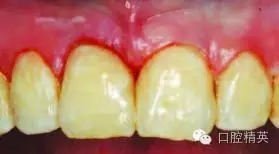

圖7:完成V類洞樹脂直接粘接修復(fù)后

圖10:術(shù)后一周表現(xiàn)

使用微填料的釉質(zhì)樹脂(色號A2)和白色調(diào)的模擬鈣化斑(圖7)。有研究顯示,使用微顆粒大小的復(fù)合樹脂,與填料樹脂相比,能減小聚合收縮,減少邊緣微滲漏。

預(yù)備剩余的V類洞和III類洞齲壞部位(圖8),并充填修復(fù)(圖9)。

一周后復(fù)診時(shí),繼續(xù)治療。由于外形恢復(fù)良好,牙齦邊緣健康明顯改善(圖10)。